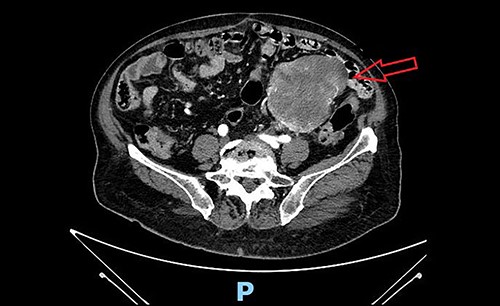

We present the case of a 79-year-old woman, whose clinical history reports hypertension, dyslipidemia, type 2 diabetes, obesity, tonsillectomy, open appendectomy, open hysterectomy and subtotal thyroidectomy. After an occasional finding of low haemoglobin level, the patient underwent a gastro-intestinal endoscopy with normal findings and subsequently complete abdomen contrast-enhanced-computed-tomography (CT) scan, which documented a solid mass in the left pelvic quadrant (sizes 84 × 92 × 110 mm) of uncertain origin. The mass was partially non-dissociable from the left round ligament and caused partial compression of the small bowel, without apparent invasion (Fig. 1). A diagnostic/curative laparoscopy was initially indicated. The patient entered the Emergency Room for sub-occlusive condition and was admitted to our Surgical Department. Sub-occlusion was treated conservatively and then, during the same hospitalization, the patient underwent open excision of the mass en-bloc with the colic segment and left adnexal tissues. Nasogastric tube was removed on post-operative day (POD) 1. Bowel opening to gas and stool occurred, respectively, on POD 3 and 4. Oral feeding was resumed on POD 3. Surgical drainage was removed on POD 7. The patient was discharged on POD 8.

Pre-operative abdominal contrast-enhanced CT scan. Solid mass in the left pelvic quadrant originating from sigmoid mesentery, partially non-dissociable from the left round ligament, is appreciable.